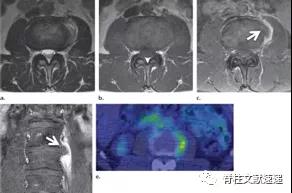

图注:背侧硬膜外椎间盘突出

图注:术前诊断倾向于硬膜外脓肿,术中见病灶呈致密纤维状,组织病理学检查显示纤维软骨盘伴反应性改变。

图注:49岁男性,极外侧腰椎间盘突出症,有黑色素瘤病史。(e) 轴位PET图像显示病灶部位有FDG摄取,怀疑黑色素瘤转移。经过3周的保守治疗,病人的病情有所好转。临床上并没有黑色素瘤诊断。